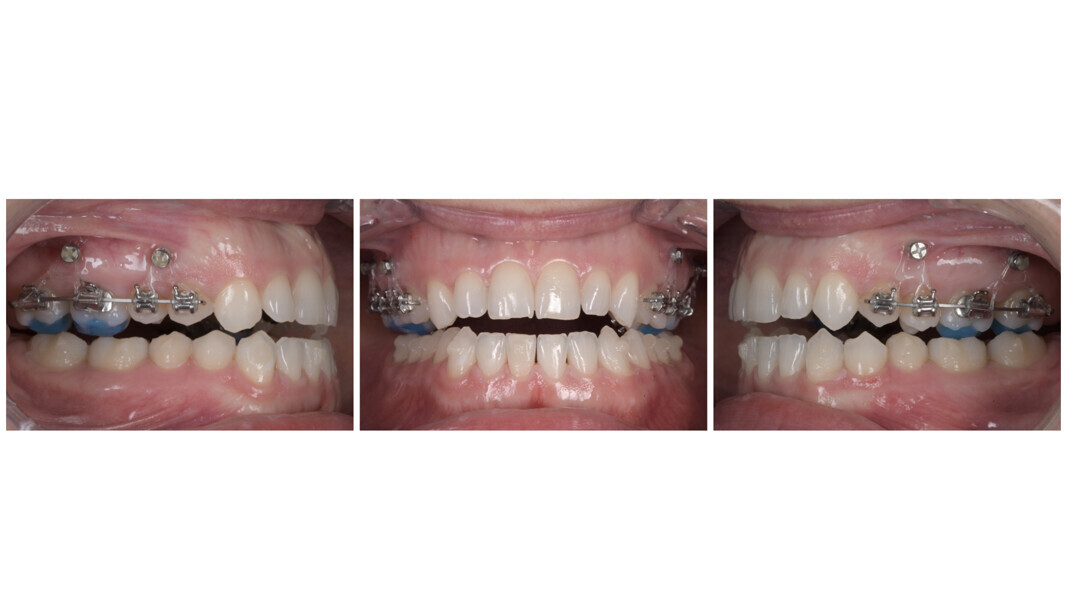

Orthodontic treatment was planned using a hybrid approach, combining fixed appliances and aligners to efficiently address the malocclusion. Treatment began with the placement of bite raisers on teeth #16, 17, 26 and 27, precisely positioned according to the patient’s arc of closure. These served the key purposes of maintaining the stable condylar position achieved by the splint therapy and of facilitating posterior intrusion to support vertical control.

Tubes and brackets were bonded to teeth #14, 15, 16, 17, 24, 25, 26 and 27 and connected using sectional arch wires. Additionally, buttons were bonded to the palatal surfaces of these same teeth. To support vertical control, eight interradicular mini-screws (1.6 × 10.0 mm) were strategically placed—four per side, buccally and palatally between the first and second premolars and between the first and second molars in the upper arch. C-chains were used to deliver intrusive forces from the screws to the brackets and palatal buttons (Fig. 43).

This first hybrid phase lasted for only three months, during which time effective maxillary posterior intrusion was achieved. As a result, the anterior open bite rapidly closed via mandibular auto-rotation, highlighting the efficacy of the hybrid technique. Moreover, this approach significantly reduced the number of aligners required and shortened the total treatment time (Fig. 45).

Once the bite had closed, treatment continued with aligners in both arches. The goals at this stage were to apply positive torque to the maxillary incisors and canines and to slightly retract the mandibular incisors, as well as to use IPR to improve the overjet and achieve ideal posterior intercuspation (Fig. 46). A total of ten maxillary and mandibular aligners were planned, followed by an additional refinement phase with another ten aligners per arch for finishing and detailing. The total treatment time, including the initial splint therapy, was 17 months.